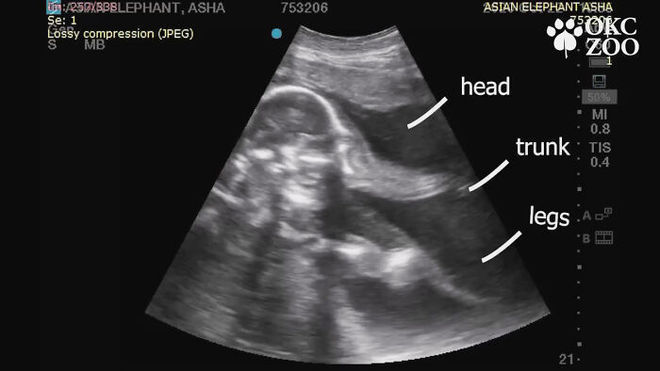

Um vídeo do exame foi compartilhado pelo zoológico de Oklahoma City, nos EUA

Asha já está com oito meses de gravidez. Na imagem acima podemos ver destacadas a cabeça, a tromba e as pernas do elefantinho